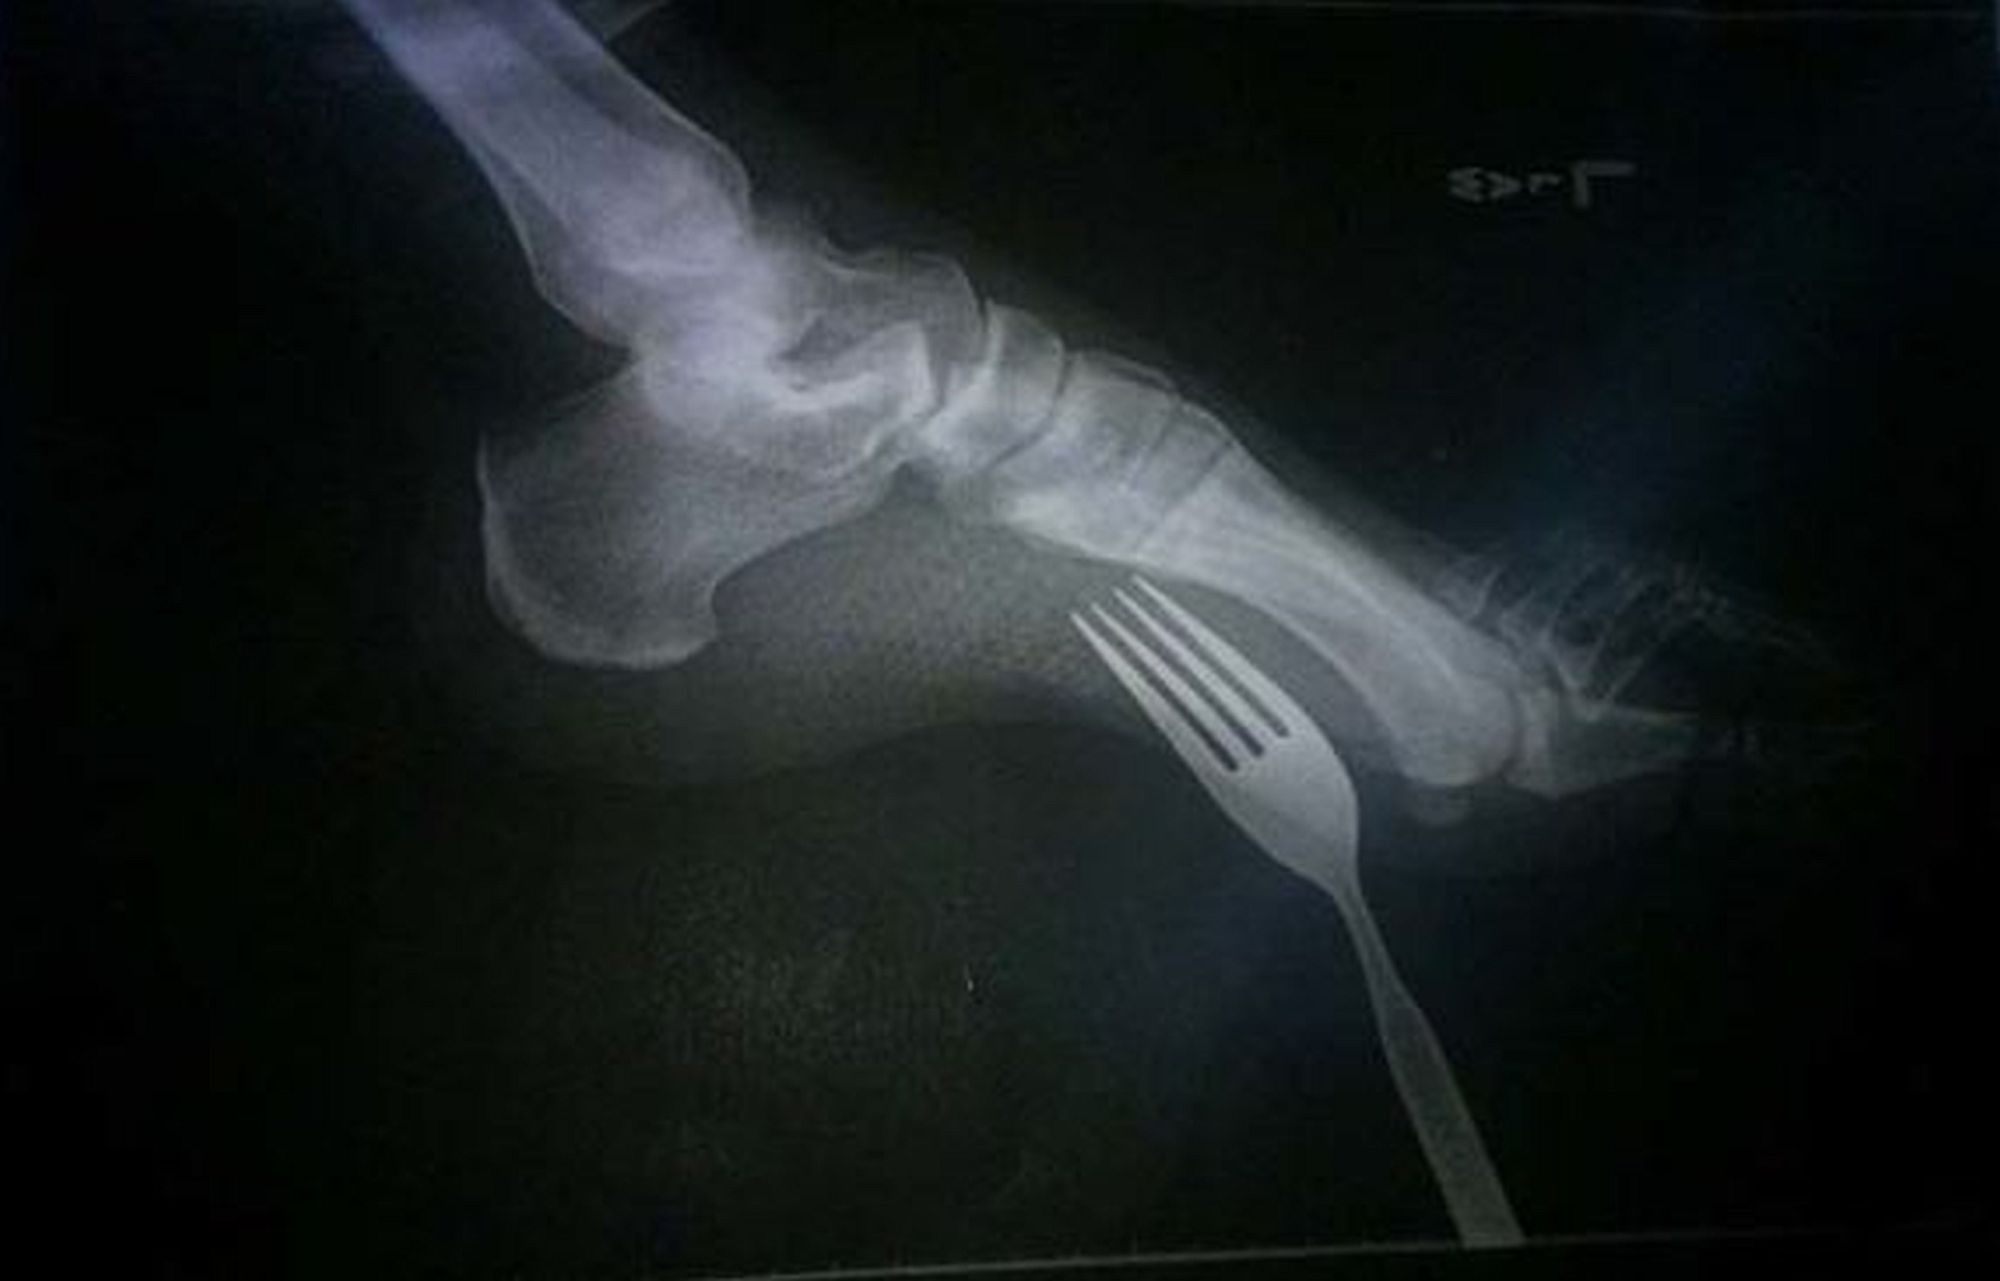

/ 8Z widelcem

Ten, kto choć raz miał złamaną nogę lub rękę, nigdy nie zapomni tego bólu. To co dopiero mają powiedzieć ludzie, którzy przyszli do lekarza z tzw. ciałem obcym? W każdej z tych sytuacji prześwietlenie nie należy do przyjemnych. Ale jest koniecznie. Uwaga, niektóre z tych "zdjęć" mrożą krew w żyłach.